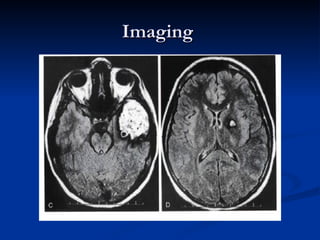

Cavernoma

   Venous Sinusoidal , thin-walled, and dilated and

have a single-cell endothelial layer

   absence of any parenchyma within the lesion

   Low flow: pressure more than cvp.

   Growth : thrombosis , endothelial proliferation

hemorrhage ( diapedesis )

angiogenic factors

Cavernoma presentation

   Headache

   Seizure : hemosiderin ring

   Hemorrhage : capsular not overt

   Focal deficit

   Pregnancy : growth

   Cummulative Risk of hemorrhage :

more in young

Imaging